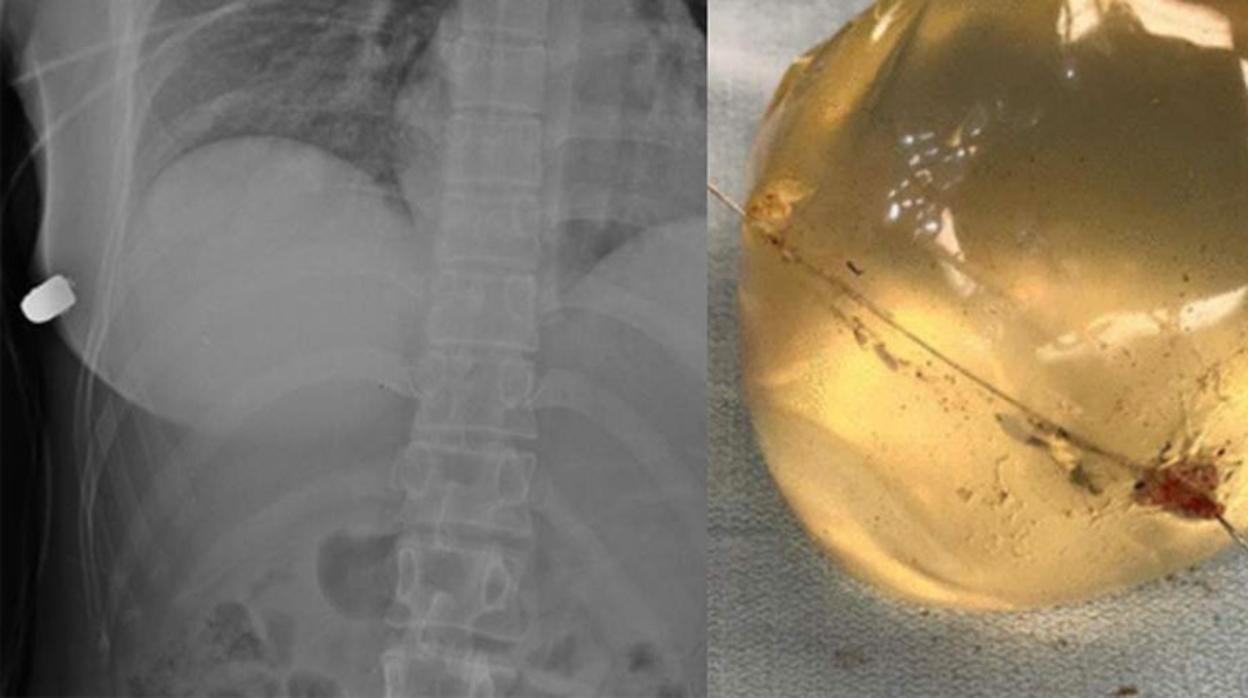

Imagen del implante atravesado por la bala SAGE

No se trata de un milagro. Un estudio realizado por varios doctores para la revista SAGE ha demostrado que la víctima no falleció en el acto gracias a que un implante mamario que se había realizado tiempo atrás desvió la bala del resto de sus órganos vitales.

Después de constatar que el implante desvió el objeto y provocó que impactara contra la pared torácica derecha, los médicos dieron de alta a la paciente.